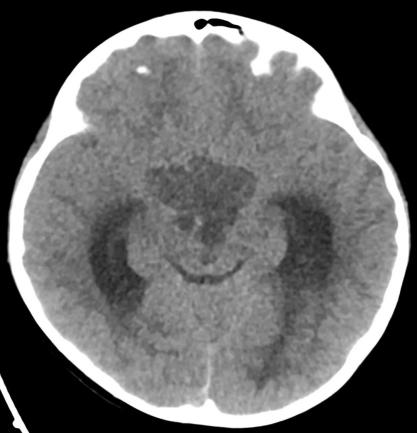

“因为教科书上介绍儿童颅咽管瘤几乎都会有钙化,但CT显示孩子的肿瘤毫无钙化迹象。”术后复盘军军的病例时,纪文元副主任医师仍觉得“不可思议”。“这个患儿颅咽管瘤十分不典型。”

CT图显示肿瘤没有钙化

若钙化,肿瘤部分呈现白色